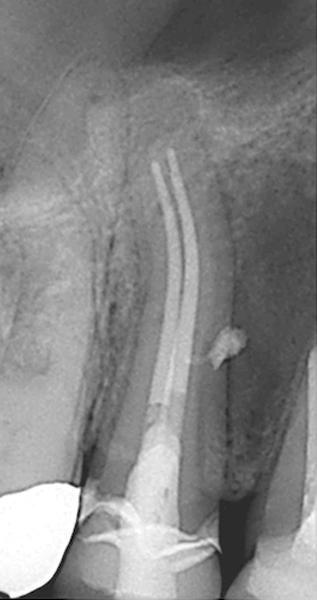

Fig 4. and Fig 5. Before and after radiographs of bioceramic sealer hydraulically moved with the gutta-percha point. Note that the cold hydraulic technique results in lateral canal “puffs” similar to the warm vertical technique. Courtesy of Dr. Gilberto Debelian.